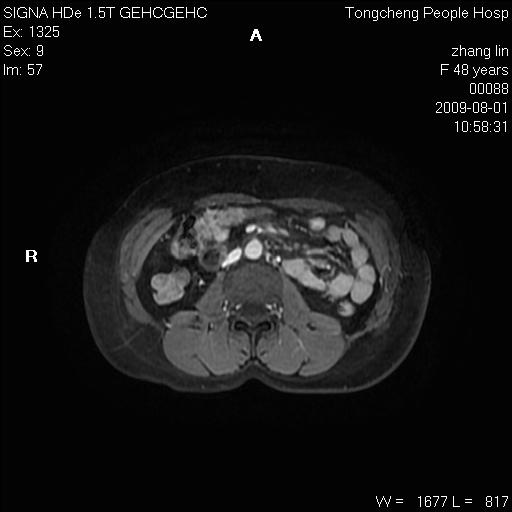

女,48岁。健康体检,彩超发现右肾占位性病变。平素健康。

临床诊断:右肾占位性病变,性质待定(囊肿?肿瘤?)。

上中腹部mr平扫+增强扫描,图像如下:

右肾上极见一类圆形病灶,t1wi呈等信号t2wi呈等高混杂信号,三期增强无强化,边界清---考虑囊肿出血。

同反相位均表现为等信号,病变无强化,考虑含蛋白的囊肿可能,弥散加权相或许有些帮助,